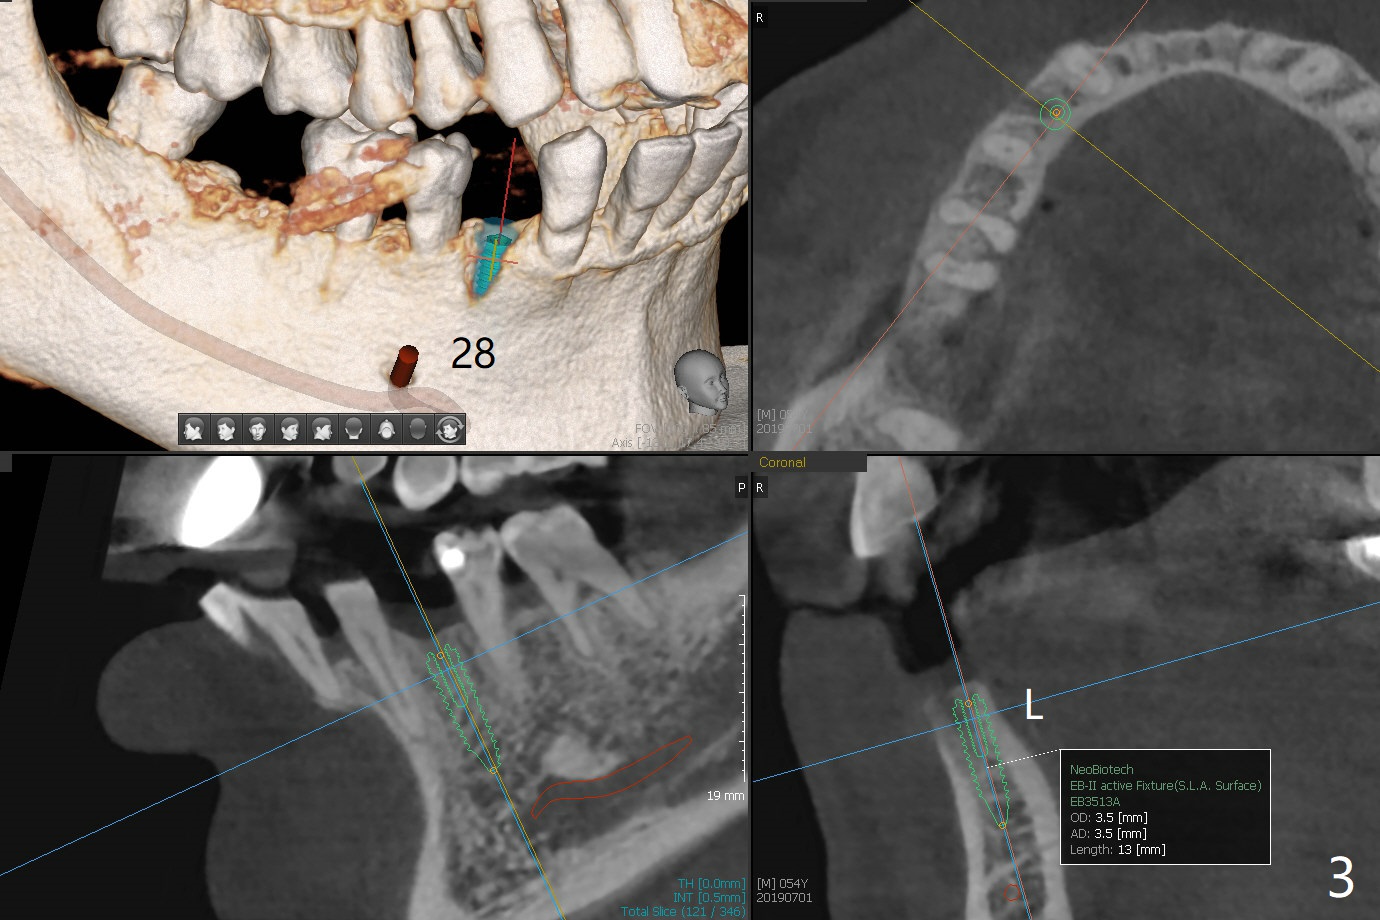

A 54-year-old man returns for #28 and 31 implants 3 months post extraction (#8,9 implants 4 years 5 months post cementation, Fig.1). The buccal plate at #28 is concave (Fig.2 *). After 2.2 mm drill to the depth as lingual as possible (Fig.3 L), use bone expanders through the guide to push the buccal plate out. Use Magic split or bone scalpels and blades to facilitate the expansion if needed. Place mixture of autogenous bone from #18 (Fig.4) and allograft buccally before implant insertion. Vertical fracture of the mesial root at #18 is an incidental finding (Fig.5 M). To avoid the impacted 3rd molar, osteotomy will be initiated as mesial as possible (Fig.6).